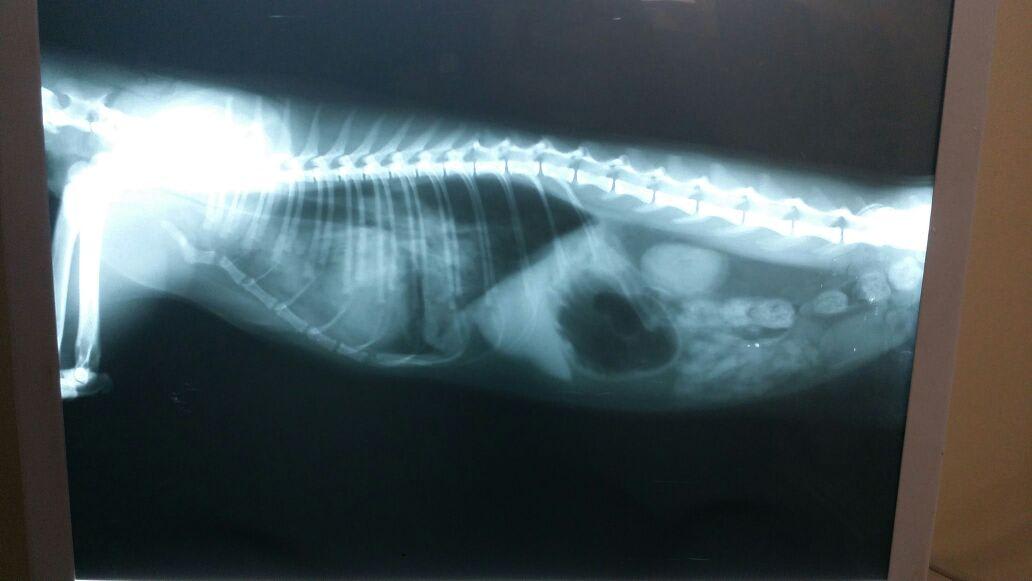

Hi doc Am searching for a second opinion please This x ray is for a 1 year old cat suffering from panting started since yesterday and now her temperature is 35 c what do you think

I would be very concerned for cardiac disease or infectious disease (pneumonia) based on those radiographs. With a temperature of 35 C (95 F) that is absolutely an emergency situation. You can see panting with cardiac disease when pulmonary edema begins to develop, which is when fluid is present within the lung tissue and does not allow for adequate gas exchange to occur. I recognize that this was posted 3 days ago, but if Sasi has not been re-evaluated by her veterinarian she needs to be ASAP to determine a treatment plan and if further diagnostics are indicated (echocardiogram, airway wash, etc.).